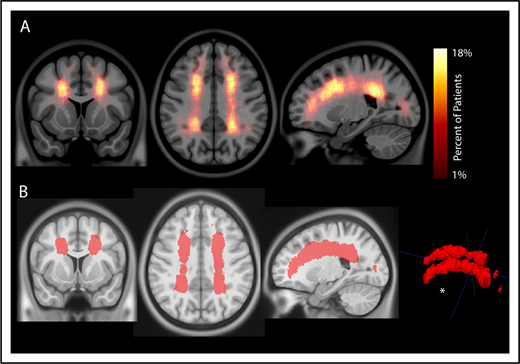

To evaluate the interaction between location and frequency of SCIs in pediatric SCA, an infarct density map from 286 participants with SCIs was created (Figure 2A). Infarct frequency within voxels ranged from 1 to 51 participants, and corresponding infarct density ranged from 1 to 18%. Infarct locations with the highest density were found in the white matter of the frontal and parietal lobes above and adjacent to the lateral ventricles.

Infarct density map from 286 children with SCA and SCIs in the SIT Trial. Infarct density was calculated for each voxel as the sum of participants with a lesion in that voxel divided by the total number of participants evaluated in the cohort. (A) Infarct densities range from 1% to 18%, with greatest densities falling in the deep white matter of the frontal and parietal lobes. (B) The infarct density map was thresholded to determine the region which encompassed SCIs from 90% of the cohort. The volume of this region was 5.6% of total intracranial volume. *SCIs for 90% of children are located within a confined region (5.6% of total brain volume).

To evaluate the spatial extent of SCIs encompassing most of the cohort, the infarct density map was thresholded to delineate the region capturing lesions from 90% of the population. SCIs from 90% of children were confined to a relatively small brain region measuring 5.6% of total brain volume (Figure 2B). The infarct density map was further analyzed for degree of symmetry between right and left hemispheres. Infarct densities for mirror voxels between the right and left hemispheres were highly symmetric (r = 0.878; P < .001; Figure 3). Most SCIs were located in white matter, with larger SCI volumes in white (median, 278 mm3; IQR, 125-772 mm3) compared with gray matter (median, 33 mm3; IQR, 3-146 mm3; P < .001). Children were most likely to have SCIs in the frontal lobes, followed by parietal, temporal, and occipital lobes (Table 2).